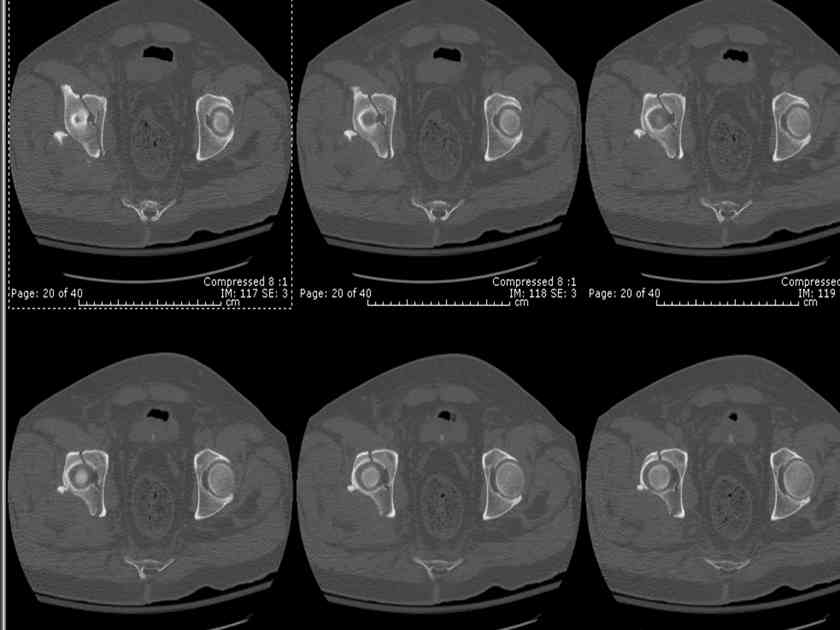

I'll include a few images of a similar injury in a similarly large male patient. This patient "showed up" in our ER c/o hip pain 2 months after being treated in the lateral position, without a quality reduction, without an anterior column transverse supporting implant, with an unbalanced plate applied too medially, with insufficient caudal segment fixation...it took over 8 hours and a 3+ l blood loss to debride the callus from front then

back, excise the HO, release his sciatic nerve, reduce the head-transverse-wall, and fix it...and now it's a staging procedure.

The 2nd example is of a motorcyclist with a transverse fracture-dislocation...he had a closed attempted reduction and placed in traction but the manipulative reduction was not concentric (not unusual for this injury pattern)...so the traction was adjusted to be just enough to disengage the head from the fracture (12#) until he could be cleared for surgery one day after injury...he was treated "urgently" then with a prone KL, clean the fracture, reduce and clamp it, screw it, support with a balanced plate, close, and enjoy...2-3hours, 400cc EBL, blah, blah, blah..